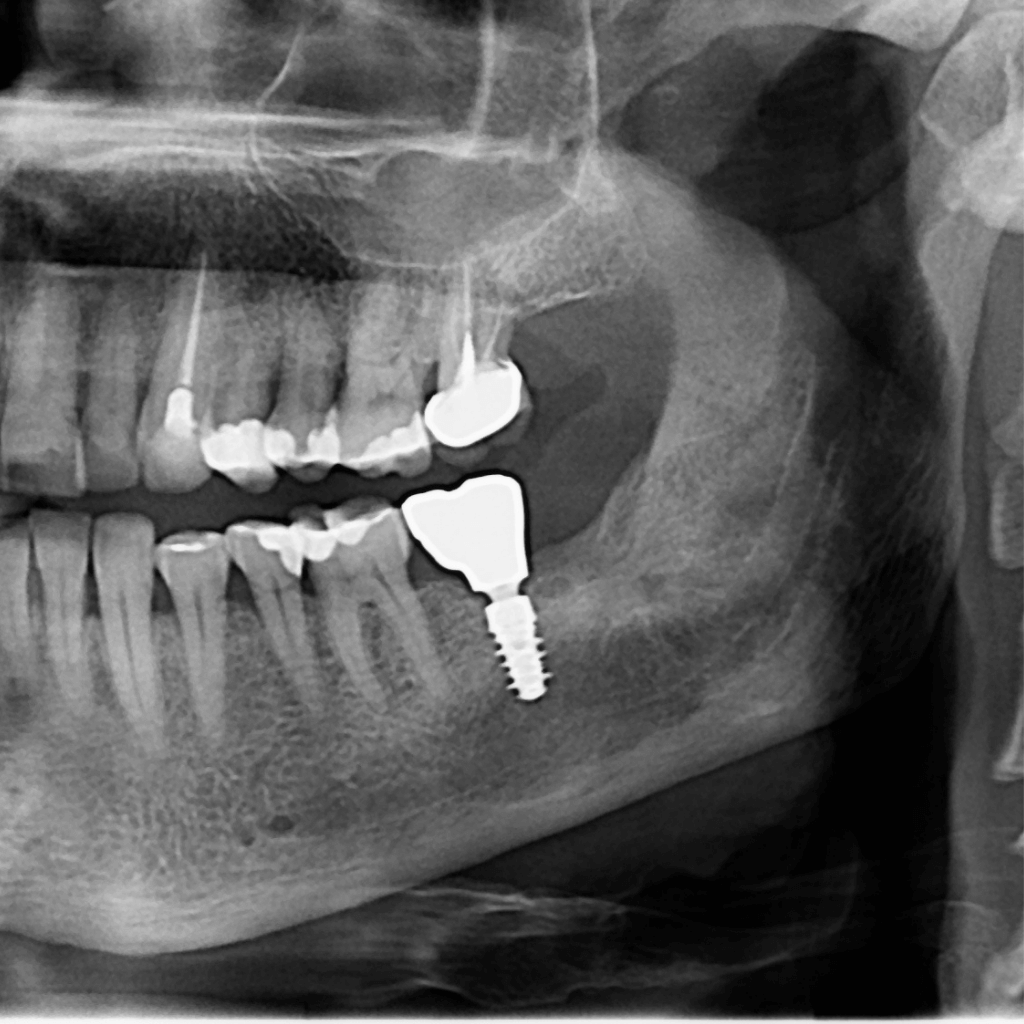

Денталните импланти са съвременно решение за възстановяване на липсващи зъби, което позволява стабилна функция и естествено усещане. Те заместват корена на липсващия зъб и служат като основа за коронка, мост или по-голяма конструкция. Имплантологичното лечение цели не само възстановяване на дъвкателната функция, но и запазване на костта и дългосрочна стабилност на захапката.